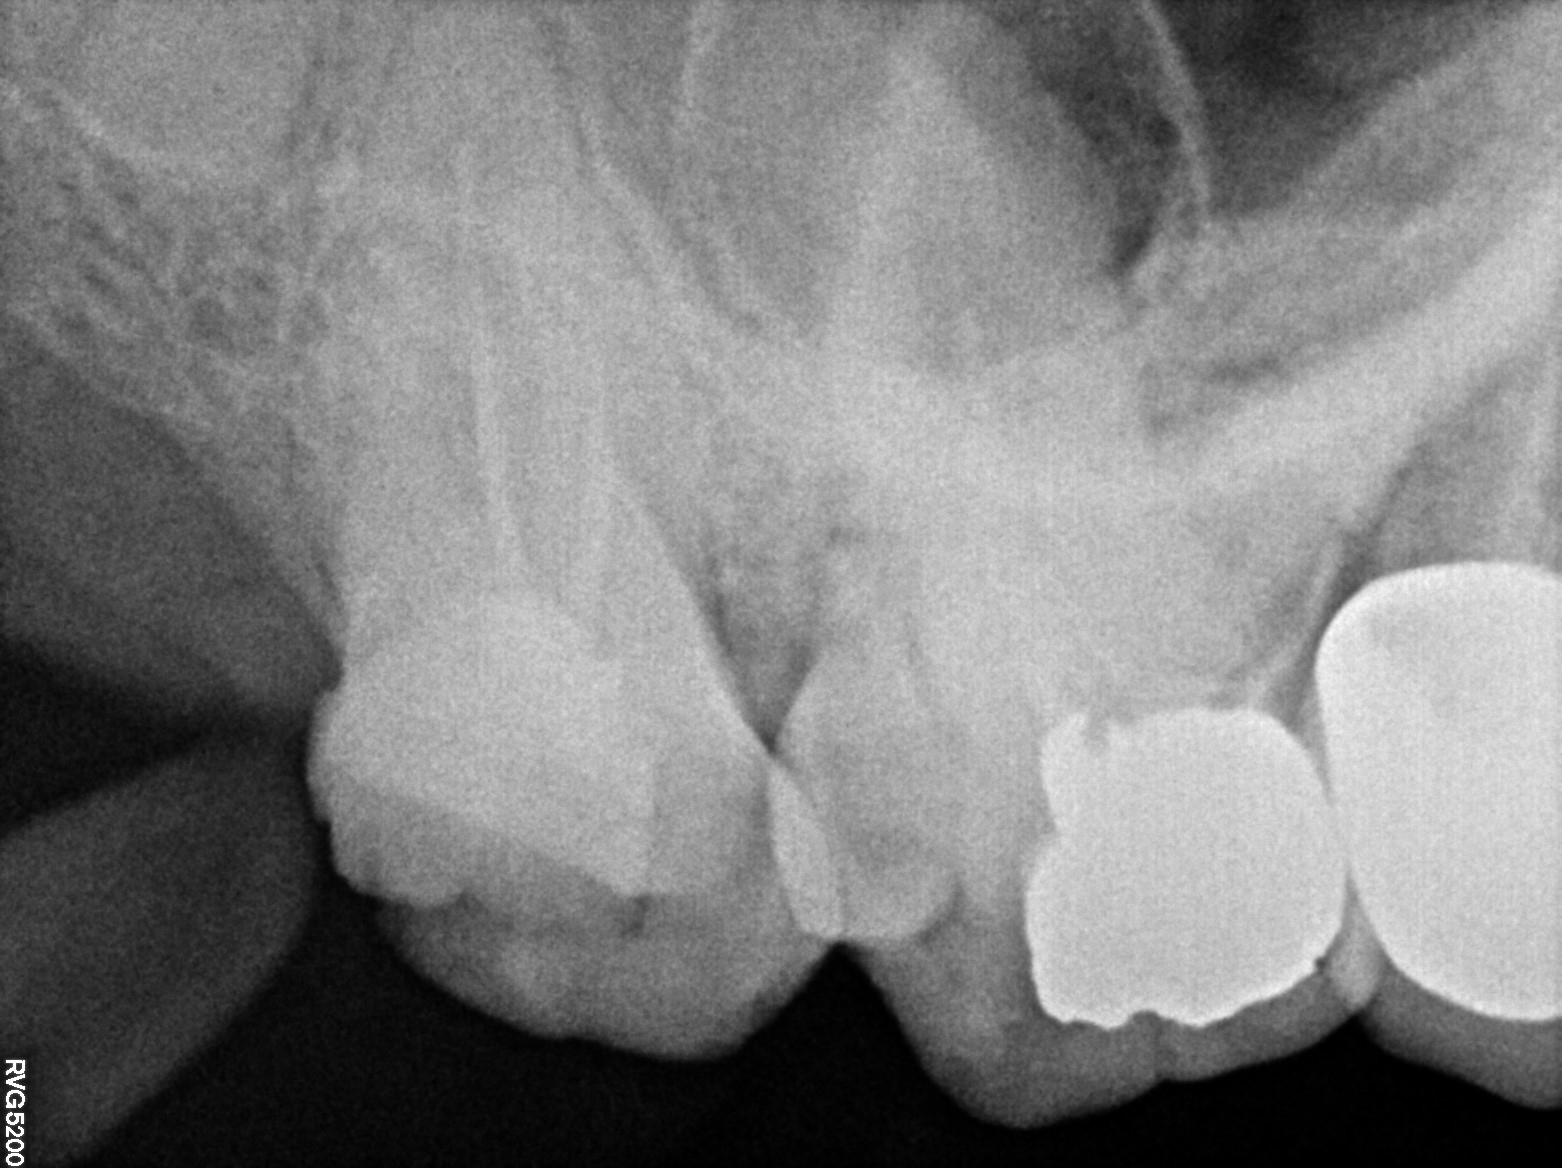

Dental Radiographs FHIR: DocumentReference · LOINC 24641-7

xray_1770449444_0.jpg

24641-7